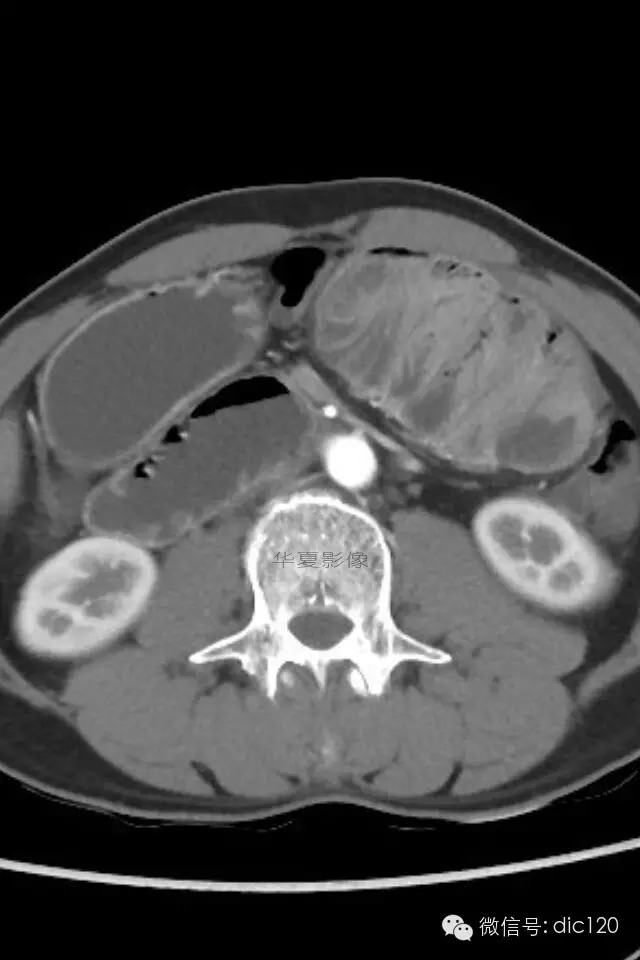

小肠禁锢症/腹茧症

肠茧症,即小肠茧状包裹症,又名:腹茧症,先天性小肠禁锢症。多为先天性畸形。

腹茧症以小肠被茧状包裹在一层异常的纤维膜内为其特征,为一种少见的,原因不明的特殊类型的肠梗阻。包膜厚薄不均,增厚处呈乳白色,包膜内小肠间或包膜间可有疏松粘连,包膜可局部增厚,形成缩窄环或束带压迫肠管形成梗阻,肠梗阻发生率约为57%,腹茧症伴腹腔内畸形率较高,约为54%。腹茧症92%的病人以肠梗阻就医,其中亚急性肠梗阻和慢性肠梗阻占71%,一些病人是在腹部手术时偶然发现本病。腹茧症女性多见,Francis总结以下情况可想到本病:1.青年女性,有不明原因的肠梗阻。2.既往又类似发作史,可自行缓解。3.常表现为腹痛及呕吐,但缺乏肠梗阻的四大典型症状。4.触诊腹部有无压痛的包块,质地软。腹茧症治疗以手术为主,充分松解粘连缩窄环,彻底解除梗阻使小肠复位或加以肠排列等。绝大多数病人术后症状消失,少数病人遗留症状,可试服用泼尼松,维生素B1治疗。

肠茧症分为两种类型:

1.单层包裹型 由单层纤维组织膜将小肠或其它脏器包裹。此种类型常包裹小肠及其系膜。手术时进腹容易,容易发生肠梗阻。

2.多层包裹型 俗称“千层饼”样包裹,其纤维层次多而广泛。手术时进腹困难,被包裹的脏器无移动性,发生肠梗阻的机会少。